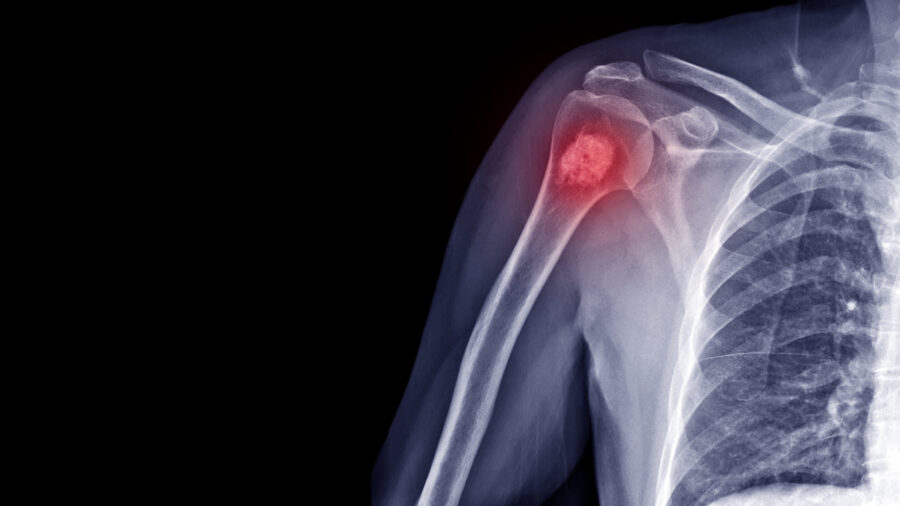

It starts when a tumor forms in a bone. It usually begins in one of the long ones in your arm or leg. As it grows, it kills normal bone cells and may spread to other parts of your body. Bone cancer is most common in children and young adults.Common Types

Osteosarcoma, the most common bone cancer, usually happens to people ages 10 to 30 and most often starts in the arms, legs, or pelvis. Ewing sarcoma also is more likely to be in kids and young adults. It starts most often in the arms, chest, legs, pelvis, and spine. People over 40 are more likely to have chondrosarcoma — usually in the arms, legs, or pelvis. Cancers like leukemia that start in marrow — tissue in some of your bones — aren’t seen as bone cancer.Rare Types